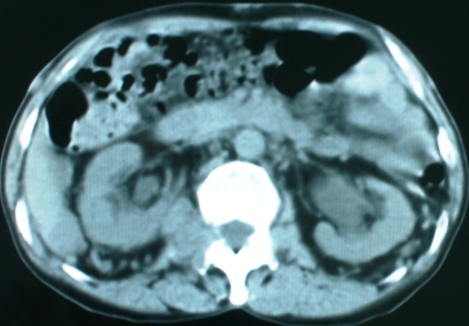

以下是引用zsl6918在2008-11-4 19:14:00的发言:[br]多发转移性改变,子宫改变不除外为原发灶